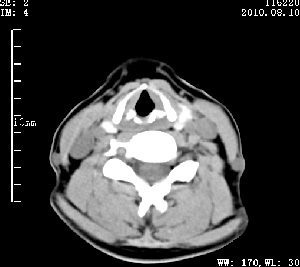

标题: CT28317:病人近几天无意间发现颈部肿块。 [打印本页]

标题: CT28317:病人近几天无意间发现颈部肿块。

甲状腺左叶局限性结节性甲状腺肿可能。建议增强扫描。

病变边界清楚,周围间隙清晰,甲状腺左叶(甲状旁腺?)肿大,右叶甲状腺腺瘤。

病变边界清楚,周围间隙清晰,左叶甲状腺肿大,右叶甲状腺小腺瘤。